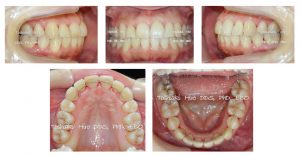

この患者さんは臼歯の遠心移動の期間を含め、1年11ヶ月で治療が終了し、矯正装置を除去しました。

舌側矯正は時間がかかるからやめたほうが良いと言う先生がいますが、それは間違った情報であるということがおわかり頂けると思います。

調整の回数は 21回でした。

写真は装置を外した当日の写真ですので、裏側の歯肉辺縁が赤くなっていますが、歯周ポケットはなく、赤い部分は1ヶ月後の来院時には綺麗に引き締まった歯肉になっていました。

治療終了から約3年後の状態です。

非常に綺麗な歯並びが維持されていることがお分かり頂けると思います。

定期チェックでお見えになったときは毎回歯石の除去を行っていますが、別途費用は頂いていません。

矯正治療前の歯周病も改善され、歯肉、骨、歯、いずれも健康な状態を保っています。